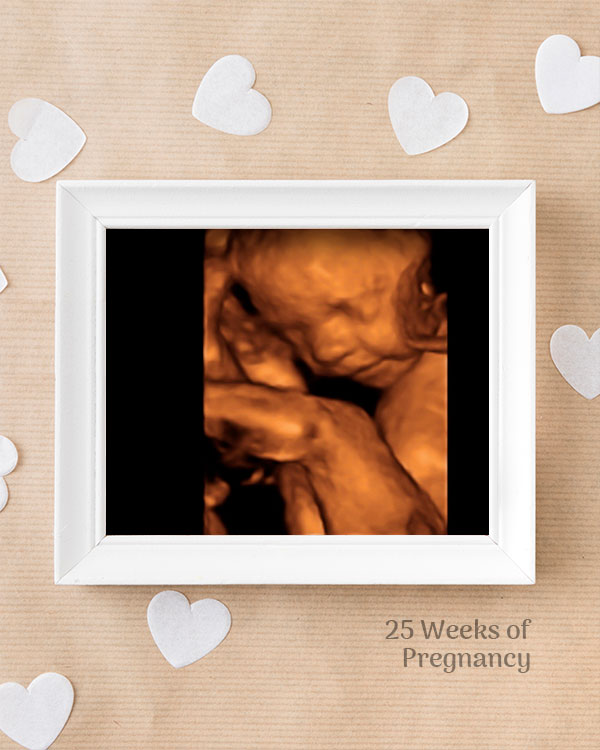

3D / 4D Baby Scan

Mediserv Diagnostics pioneered 4D scanning in the Malabar region. These advanced scans provide realistic images of the baby, allowing detailed evaluation of fetal structures and movements while creating a meaningful bonding experience for parents.